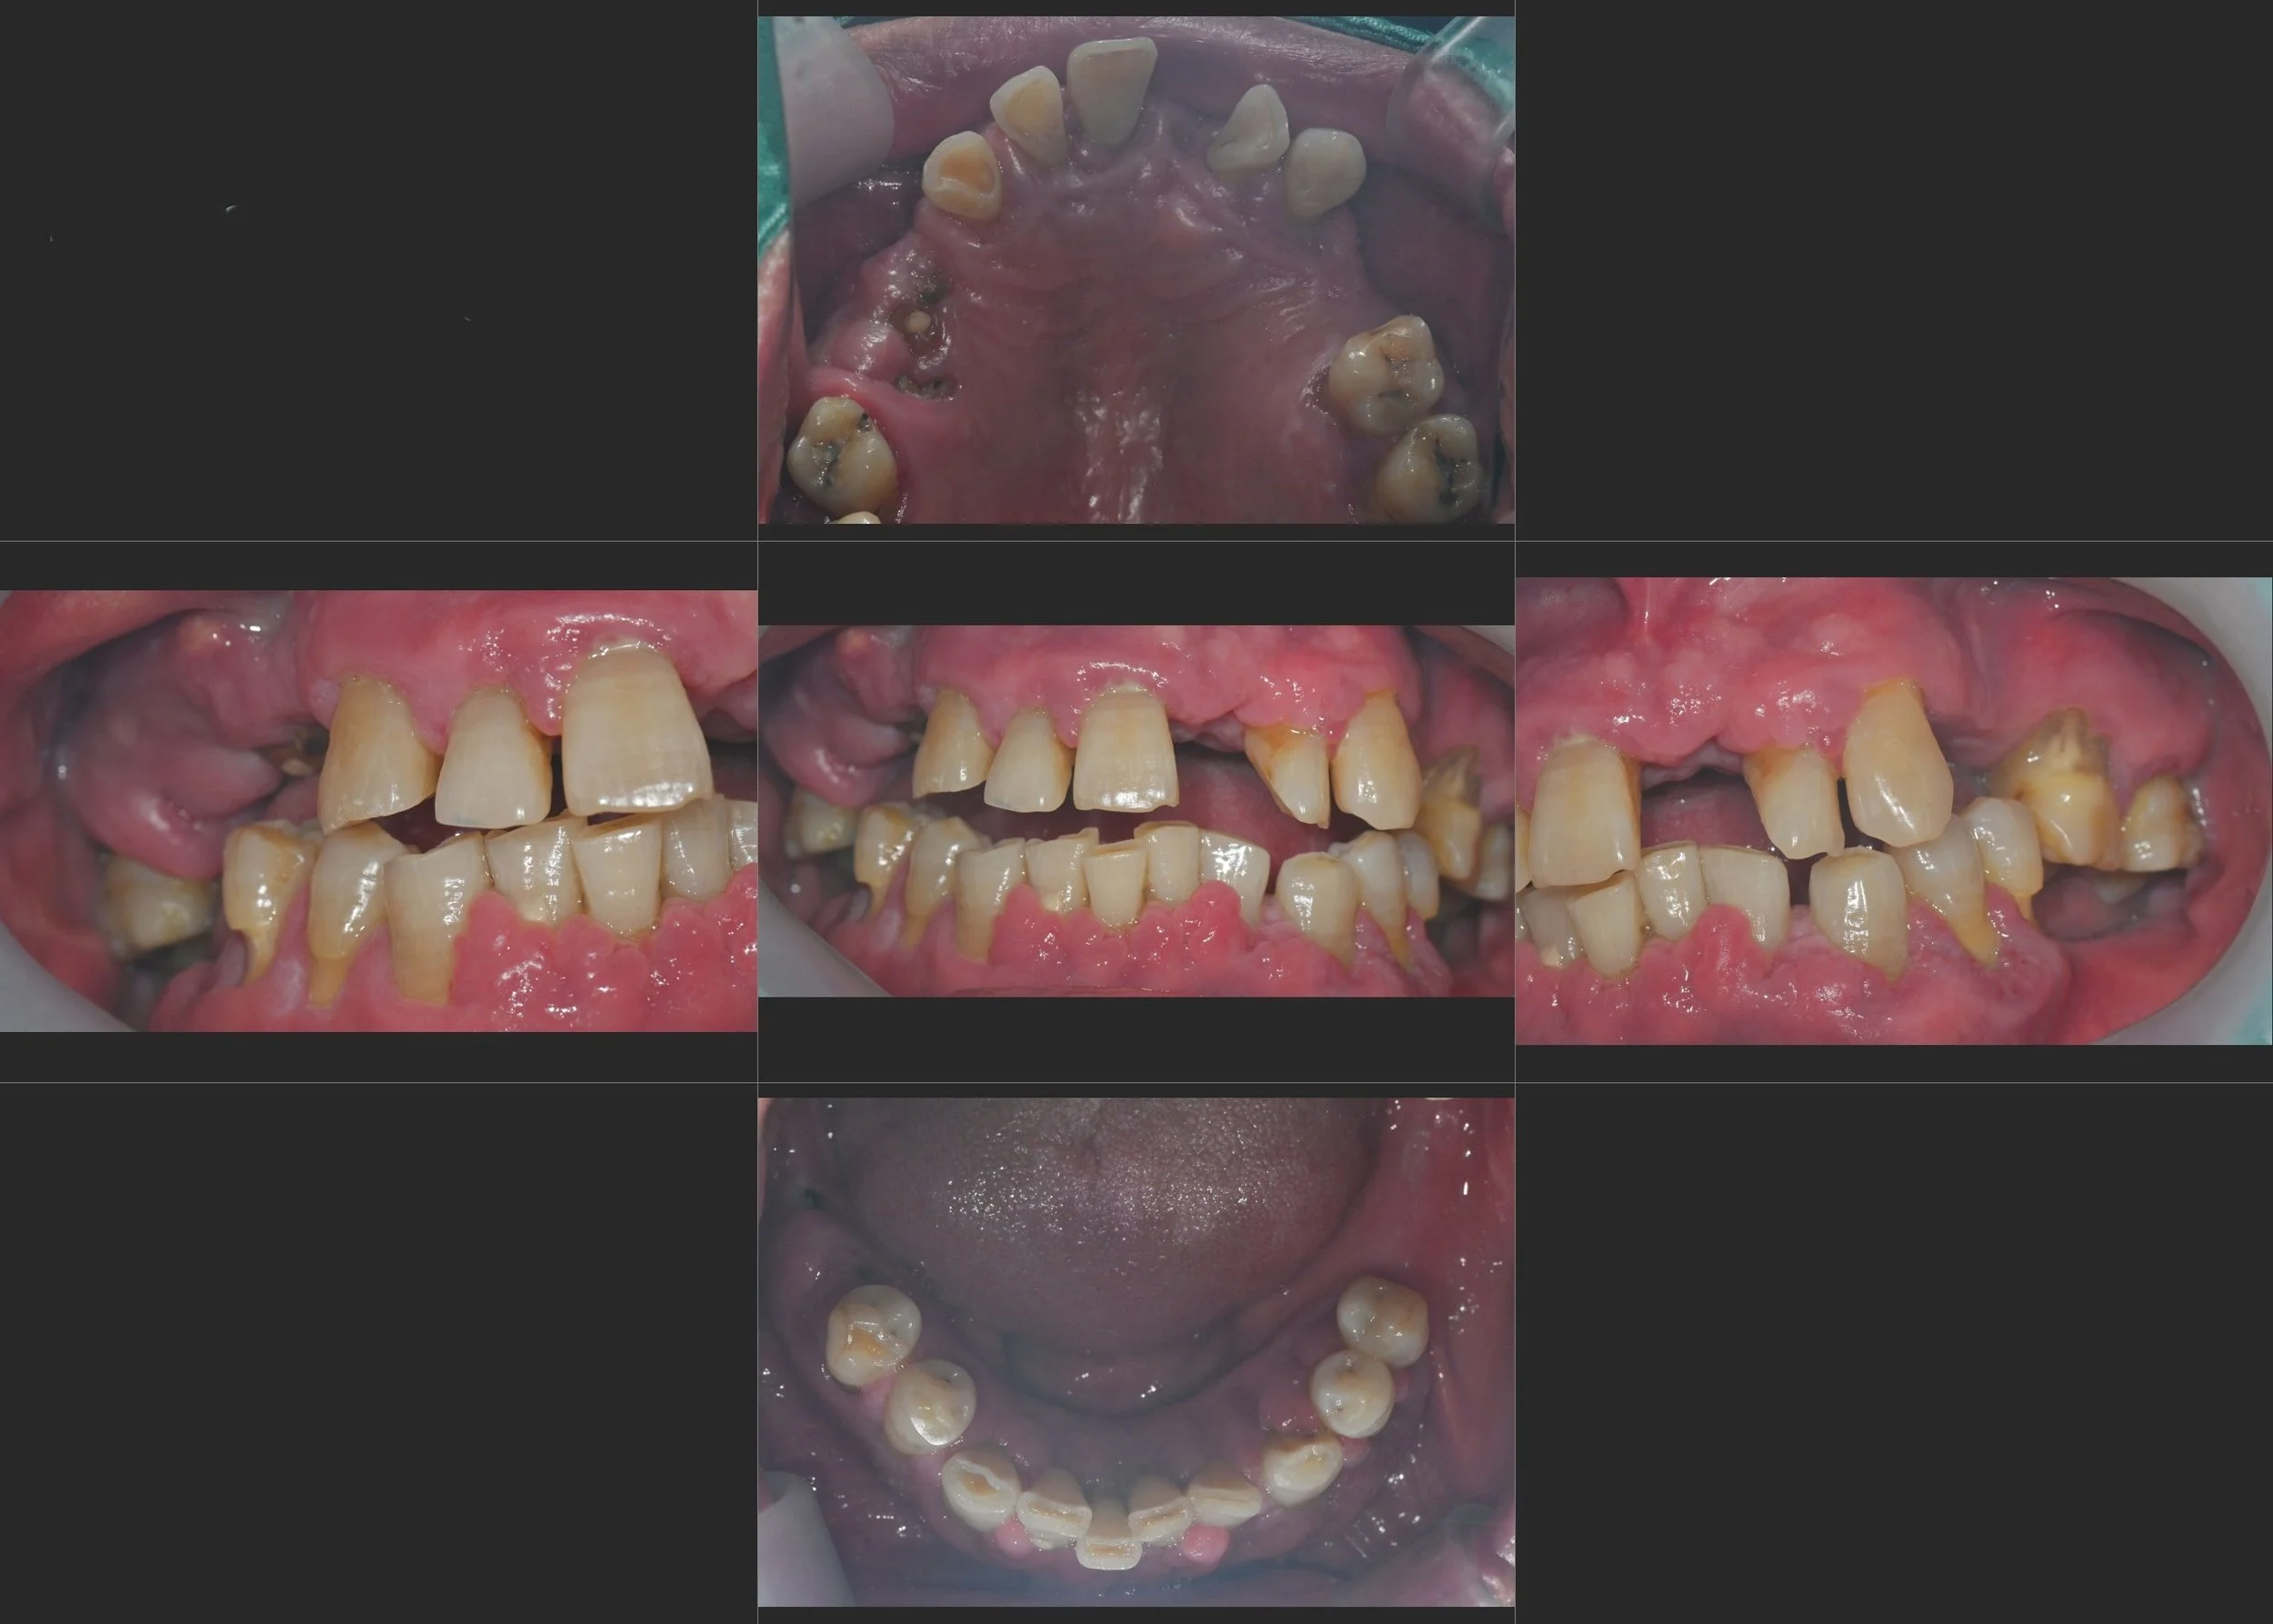

INTRA ORAL - BEFORE

A male patient in his 50s presented with a severely compromised dentition. Years of progressive periodontal disease had led to:

• Generalized Tooth Loss: Multiple missing units in both the maxillary and mandibular arches.

• Loss of Occlusal Relationship: The lack of posterior support had caused a total breakdown of the bite, making mastication nearly impossible.

• Periodontal Instability: Severe horizontal bone loss and increased tooth mobility were evident across the remaining dentition.

While a full-arch implant-supported solution (such as All-on-6) was a viable surgical alternative, the patient expressed a strong desire to preserve his remaining natural teeth wherever clinically possible.